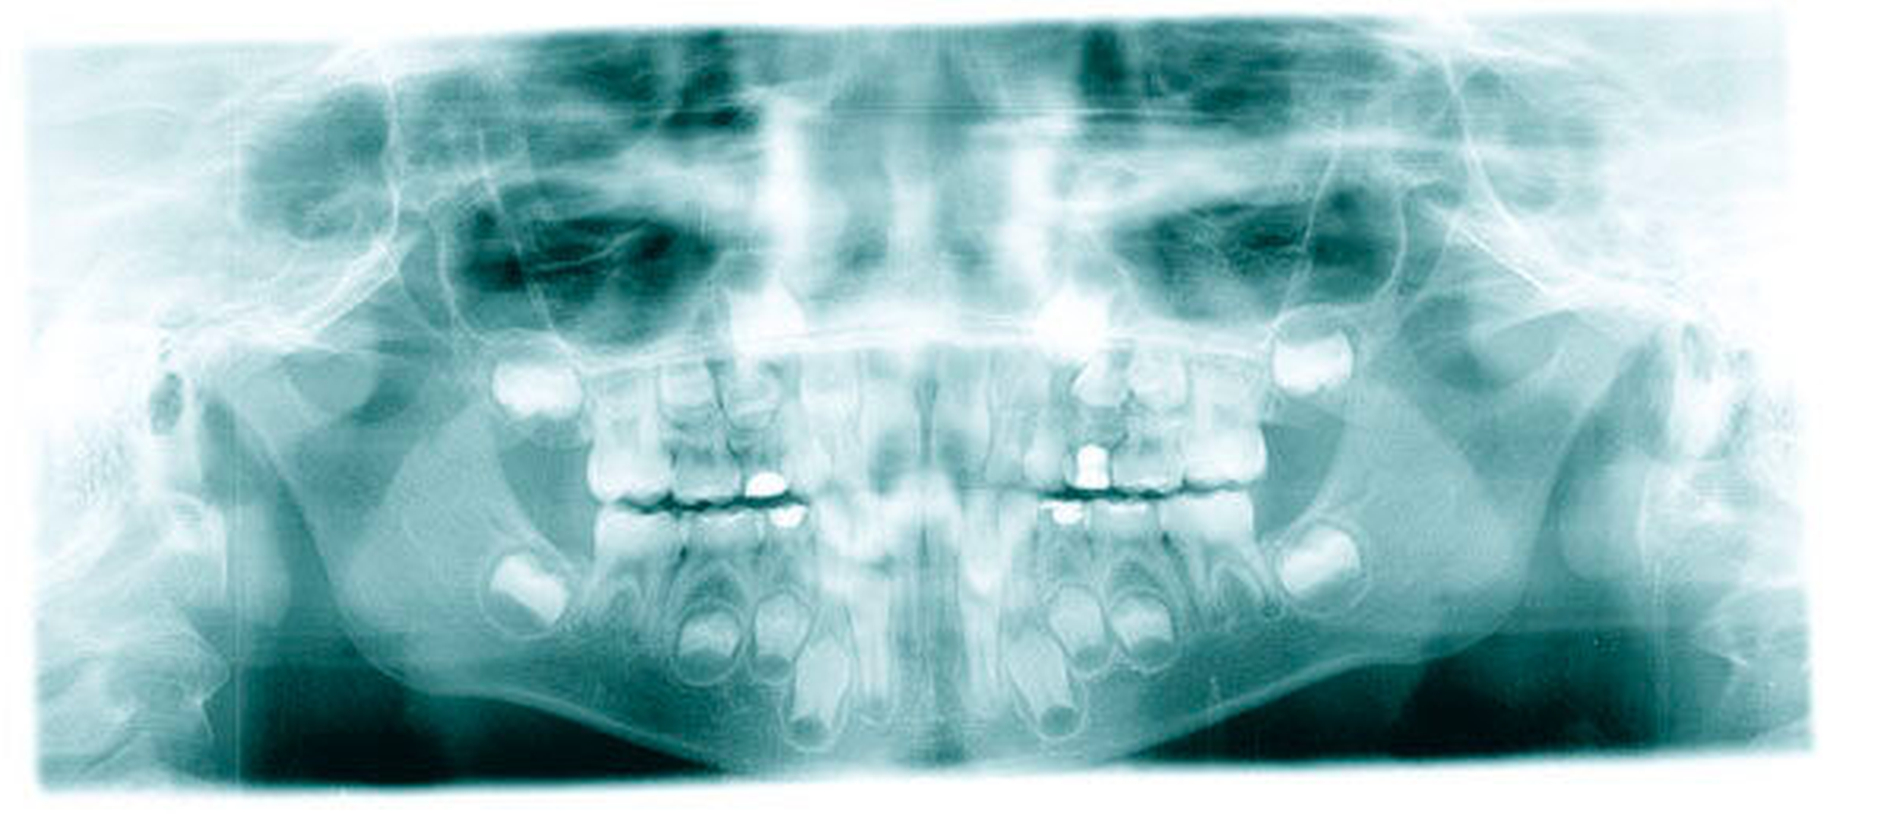

Ausgangsbefund:Während der extraorale Befund unauffällig war, zeigte der intraorale Befund ein kariöses Milchgebiss (Abbildungen 1 und 2).

Behandlungsphase im ZFZ:Im Juni 2008 fand die Milchzahnsanierung in ITN statt. Dabei wurden die Füllungstherapie sowie eine Pulpotomie durchgeführt. Anschließend wurde der Patient zur regelmäßigen Kontrolle und Intensivprophylaxe wieder an den Hauszahnarzt zurücküberwiesen.

Zweiter Befund nach drei Jahren:Im April 2011 stellte sich der Patient erneut im ZFZ vor. Mittlerweile war der Patient sieben Jahre alt und im beginnenden Wechselgebiss zeigten sich Schmelzhypoplasien der Sechsjahresmolaren (Abbildungen 3 bis 5). Da die Zähne starke Empfindlichkeiten und zunehmende Substanzverluste trotz versuchter Fissurenversiegelungen aufwiesen, hat der Hauszahnarzt mit den Eltern entschieden, diese weiter versorgen zu lassen. Somit wurde der Patient wieder ans ZFZ überwiesen zur erneuten ITN-Behandlung.